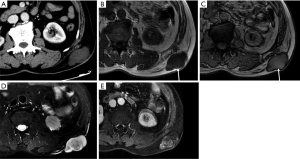

Metastases

Metastases are the most common malignant lesions encountered in the anterior abdominal wall. The imaging characteristics of abdominal wall metastases are nonspecific, but they often resemble the known primary disease in other sites. The single most consistent discriminating feature is the rapid growth of lesions in a known cancer patient, who is usually at an advanced stage and has multiple other metastases. Metastasis of the umbilicus is known as Sister Mary Joseph’s nodule and typically originates from cancers of the gastrointestinal tract and ovary (52-54). The proposed metastasis route of Sister Mary Joseph’s nodule is along with the remnant structures at the umbilicus (55,56). Metastasis to the surgical wound or laparoscopic trocar site and needle-tract seeding after radiofrequency ablation also lead to the formation of abdominal wall metastases (Figure 10). These specific metastases may not be associated with widespread disease in contrast to hematogenous abdominal wall metastases.

Although the clinical diagnosis of abdominal hernias is relatively easy, CT or MRI can help distinguish between abdominal hernias and abdominal or abdominal wall tumors by showing the herniation of fat or intestines through the fascial defect, in addition to complications of intestinal fistulas, such as ischemia and obstruction (59). As an interesting finding in our routine work, CT can be used to identify the inferior epigastric artery and can help distinguish oblique and direct hernias, which is important for surgery (Figure 12).